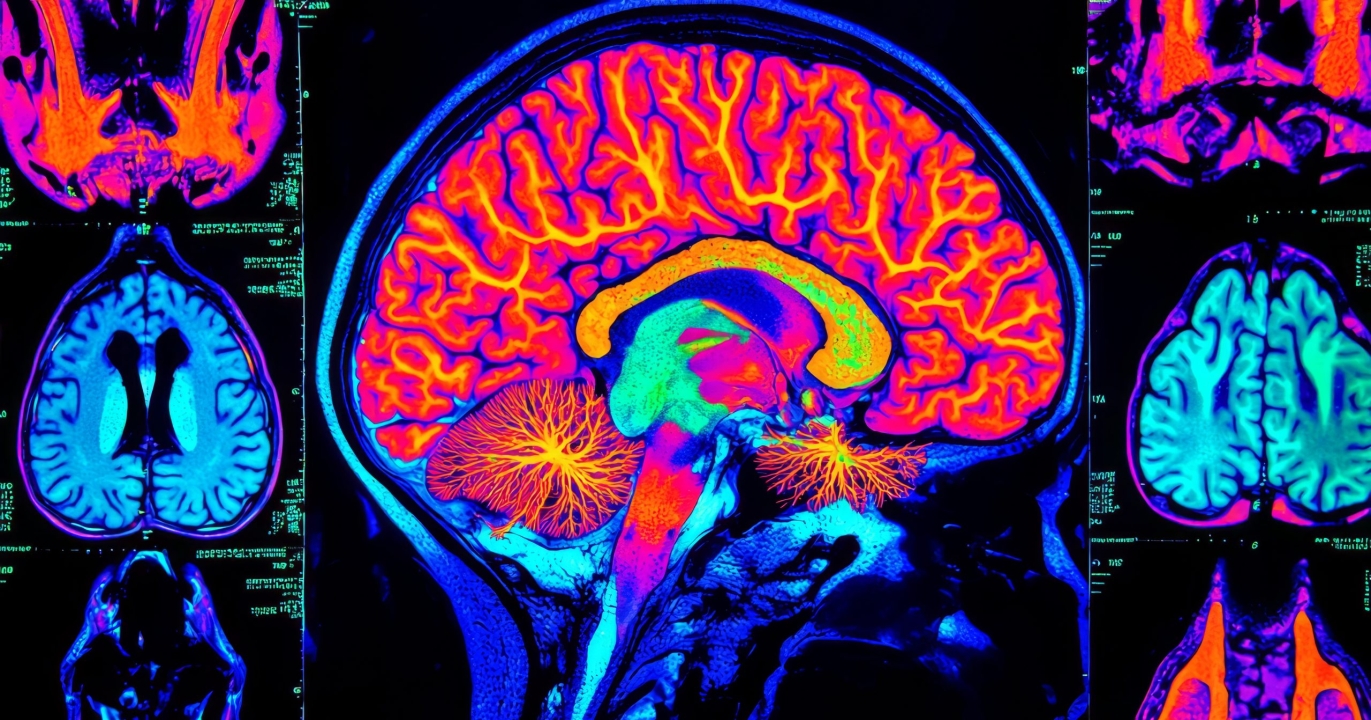

Des signaux d’alarme dans les scans cérébraux

Grâce à des techniques avancées d’imagerie cérébrale et à des tests métaboliques, les scientifiques ont pu observer ces changements en temps réel. Dès la quarantaine, les scans montrent des signes de stress dans les cellules cérébrales, causés par leur incapacité à métaboliser correctement le sucre. Ce stress se traduit par une inflammation légère mais chronique, qui endommage progressivement les neurones. À mesure que nous approchons de la fin de la soixantaine, cette inflammation s’intensifie, entraînant une accélération du déclin cognitif.